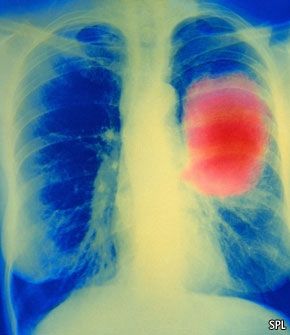

找到克服癌症的方法,是人类基因组计划带给人们最大的希望之一。理论上,只要找到出错的基因,就能研发出针对它的特定药物。事实上,这些期望正在被逐步实现。就在上个月美国食品药品管理局批准了一种名为Xalkori(通用名:克里唑蒂尼)的新药上市,用于治疗非小细胞肺癌(最常见的一种肺癌)。Xalkori能够抑制由编码信号分子间变性淋巴瘤激酶基因的突变体所导致的癌细胞的增长。3-5%的肺癌患者体内存在这种突变。临床试验中,大约一半受试者在服过此药后体内癌细胞数量显著减少。